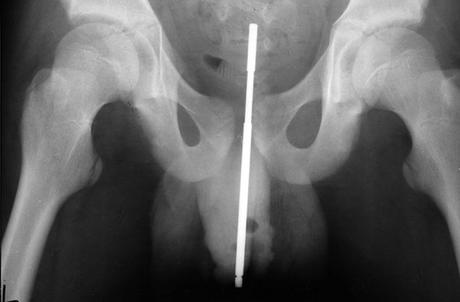

Una vez que haya viajado a la sala de emergencias después de esta inserción de cuerpo extraño, ocurrirán una serie de eventos para ayudar a los médicos a comprender lo que ha ocurrido. Se le harán preguntas, el médico tendrá que visualizar lo que ha ocurrido sin tocar el objeto para limitar el daño y tendrá que realizar estudios de imagen para tener una comprensión clara de lo que ha ocurrido.

El último procedimiento que se realiza para eliminar el objeto depende completamente de qué y dónde se puede encontrar el objeto. Es posible que deba someterse a una cirugía para extirpar algunos de los músculos y ligamentos que podrían afectar al objeto. Lo que también sería necesario probablemente sería una uretrografía retrógrada. Esta es una evaluación médica donde se insertará un tubo con una cámara en la uretra para verificar si hay daños. También puede extenderse hacia la vejiga para evaluar mejor el daño interno potencial que podría haber ocurrido.